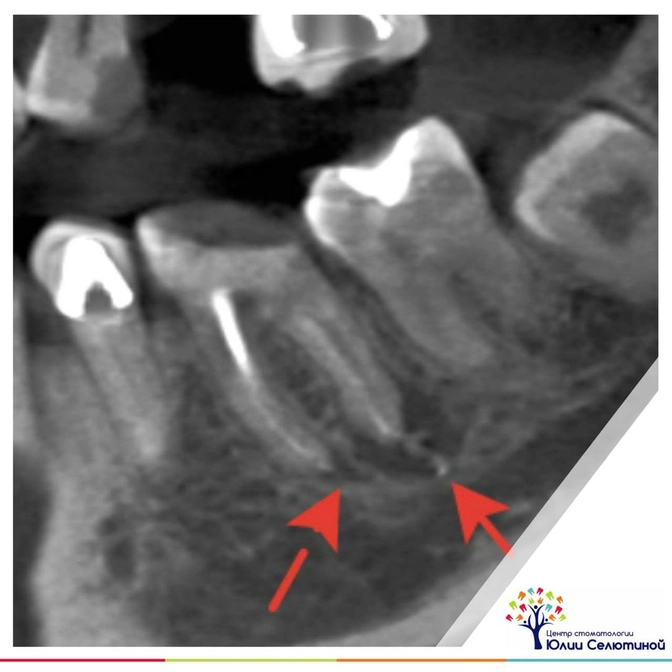

Когда через корневой канал в костную ткань челюсти попадают болезнетворные бактерии, то начинается воспаление.

Наша иммунная система пытается его сдержать и образует вокруг полости с патогенной микрофлорой плотные стенки.

Так образуется киста.

Ее размеры от 1 мм до 2 см.